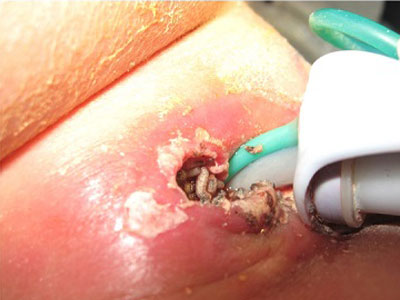

Furonküler Miyazis: Klinik olarak çok ağrılıdır ve apseye benzer. Ortasında sürekli akıntı gelen bir delik bulunur. Çevresinde ödem, lenfanjit ve yerleşim yerine göre LAP (lenf bezi büyümesi) olabilir. İnsanlarda furonküler miyazise neden olan etkenler; Dermatobia hominis, Cuterebra ve Cordylobia anthropophaga'dır. Larva çıkarıldığında klinik tablo hızla düzelir.

Tüm miyazis türlerinde tedavi, forseps yardımıyla larvaların çıkarılmasıdır. Çıban şeklindeki yaralara veya göçücü deri miyazisine neden olan larvaların arka uçları lezyonun içinde görünür. Nefes alma organları olan spirakular plaklar dışarıda kalır. Bu tür larvaları temizlemenin en iyi yolu, üzerini vazelin gibi bir maddeyle kaplayarak nefes almalarını engellemektir.

Furonküler miyaziste ise giriş deliği hafifçe genişletilerek larvaların çıkması sağlanır.